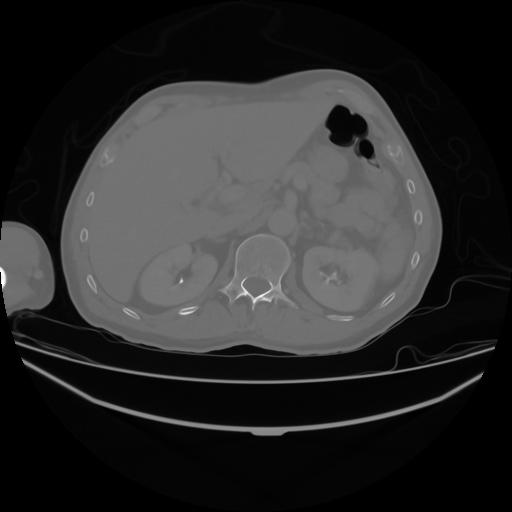

4 CUERPO,CE,Axial,3.0,CUERPO,,